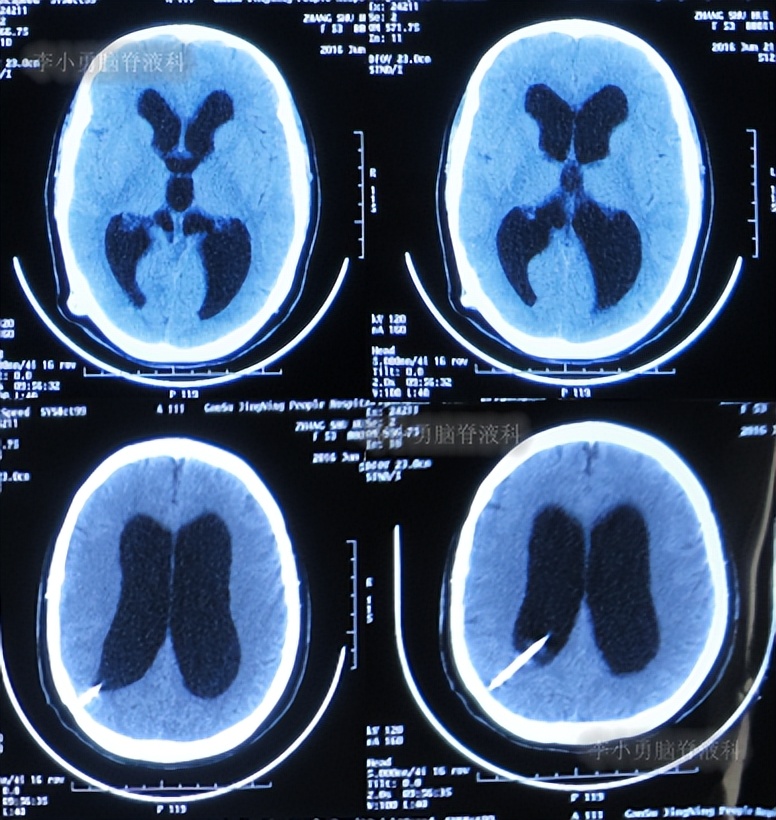

患者2014年6月20日出现持续头晕的症状,不能自行缓解,于2014年6月24日和6月26日分别就诊于甘肃省平凉县某医院和陕西省西安某医院,进行了头颅MRI和头颅CT示脑室扩张,脑积水( 图-1 、 图-2 )。

图-2: 2014年6月26日头颅CT

第2次出院后4月余即2016年6月7日,因第3次“发热”就诊当地某医院中医门诊,经中医治疗近两月时间。于2016年6月21日复查头颅CT:幕上脑室仍扩张( 图-7 )。治疗期间发热曾缓解,但之后发热仍反复。

图-7: 2016年6月21日头颅CT